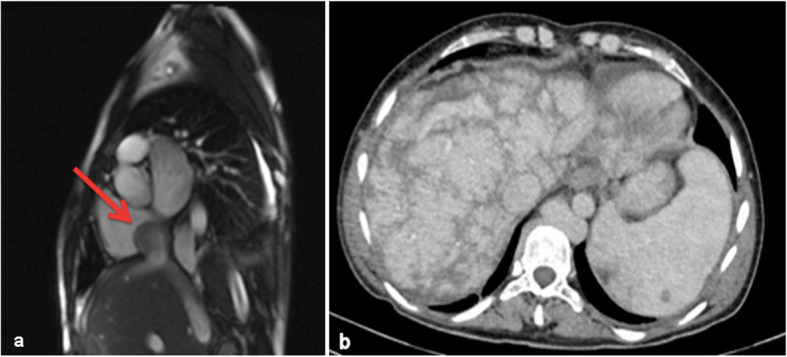

At admission, the patient’s clinical examination revealed a markedly distended abdomen with prominent superficial veins, bilateral pedal edema and hepato-splenomegaly. There was no jaundice. Clinical presentation was highly suspicious for BCS. ECHO (transthoracic and trans-esophageal), followed by MRI, revealed a membrane, dividing IVC inflow and right atrium, without communication (Fig. 2).

Fig 2.

NMR: a IVC dilated (3,5–4,1 cm) separated from RA with a 3 mm thick membrane (arrow) obstructing the flow, b dilated hepatic veins